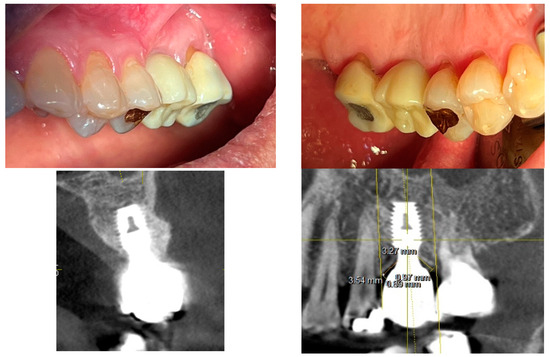

Figure 12 presents clinical images that highlight peri-implant soft tissue adaptation in SPI cases. These images were taken after the prosthetic component was removed or before placement, providing an unobstructed view of the peri-implant biologic width (or STA).

Figure 12.

Clinical images of peri-implant soft tissue showing biologic width adaptation.

Compared to epi- or equicrestal placements, SPIs generate a larger transmucosal soft tissue area, which contributes to

- Improved peri-implant soft tissue stability